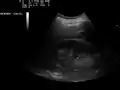

- Ultrasound of liver (left side of the image) and right kidney (right side of the image) and Morison's pouch, not containing fluid

- Ultrasonographic view of the abdomen demonstrating fluid within Morison's pouch